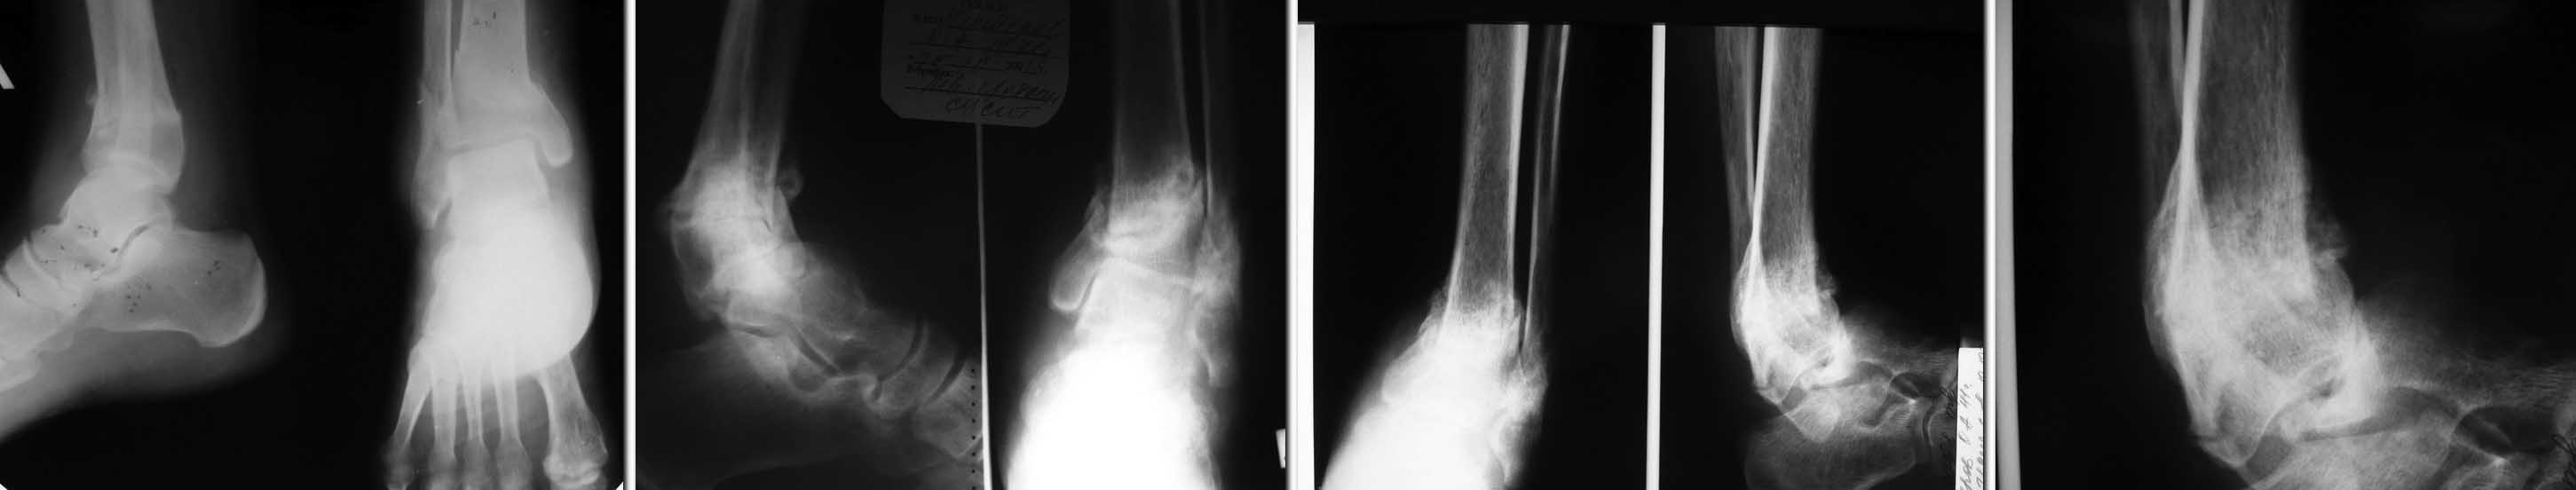

Патологический перелом голени с исходом в вывих

в начале лета сего года подвернул ногу. Появились умеренные боли при ходьбе, постепенно усиливались, через пару недель обратился в поликлинику к хирургу. Выполнена р-графия (1 снимок) Выявлен перелом, рекомендовано "ходить потихоньку с тростью" (со слов пациента). В октябре повторное обращение и контрольная р-графия из за усиления болей - выявлен ложный сустав, (снимок 2 ) Пациент начал ходить по консультантам. К нам обратился к декабрю, боли усилились значительно. Р-логически - полный передний вывих стопы (последняя пара рентгенограмм), однако пациент ходит с тростью. Возникли вопросы: первый и главный - как помочь?

Мы обсуждали вариант артродеза голеностопного сустава, но может еще есть варианты?

- Ждать ли проблем с консолидацией в зоне артродеза из-за наличия срастающегося перелома рядом?

-может операцию отложить до сращения ложного сустава, или пытаться всех зайцев убить сразу большим костным трансплантатом или мощным фиксатором...